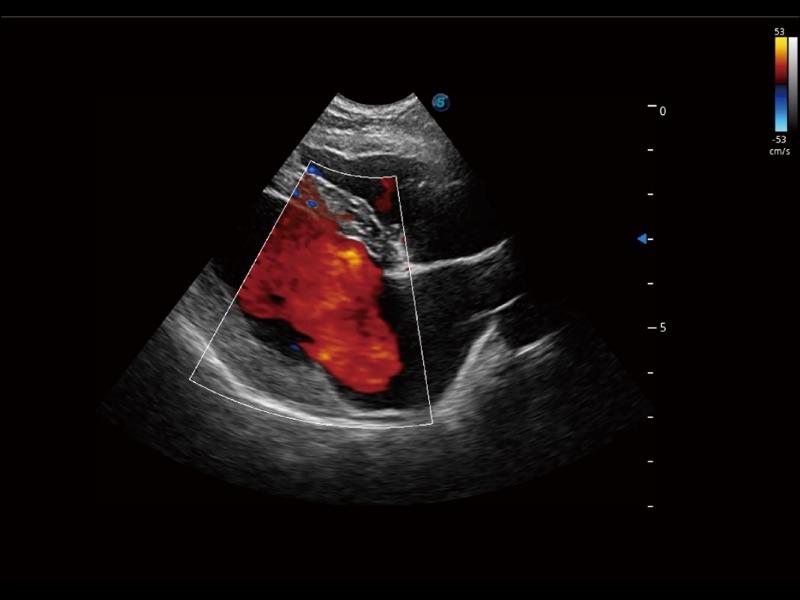

通过色彩血流和实时宽景相结合,可观察到完整的静脉或动脉的血流,方便医生检查。实时扫查过程中,如有任何操作失误也可以很容易地进行回扫擦除,而不会中断扫查。